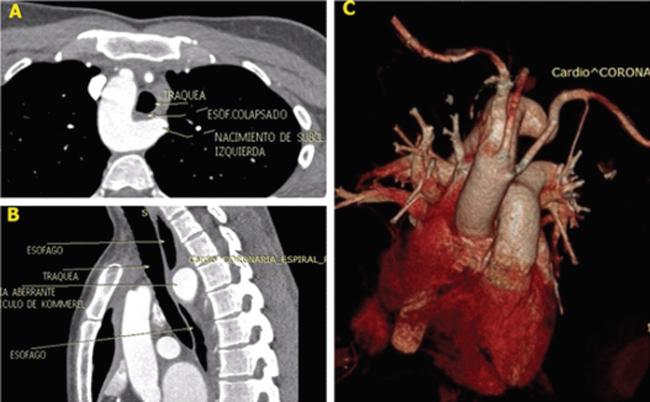

Las imágenes corresponden a una mujer de 40 años, que consulta por sensación de disfagia, acidez y precordialgia atípica. Se realiza una angiotomografía de aorta torácica donde se observa la presencia de arco aórtico derecho y anomalía en el nacimiento de los vasos supraaórticos. En la figura, se observa el nacimiento desde proximal a distal de las arterias carótidas, que se originan en orificios separados, luego la arteria subclavia derecha y, finalmente, surge la arteria subclavia izquierda desde una dilatación de 25 mm x 19 mm. Esta última cruza al lado contralateral por detrás del esófago, y lo comprime parcialmente junto al divertículo.

A. Angiotomografía de tórax. Corte axial al nivel del cayado aórtico. Se observa el arco aórtico derecho con un divertículo que comprime esófago (asterisco). (T: Tráquea; ASI: Arteria subclavia izquierda). B. Se observa lo mismo desde un corte sagital de la angiotomografía (E: Esófago). C. Imagen de reconstrucción tridimensional desde una vista anterior en la que se observa la emergencia de los vasos supraaórticos.